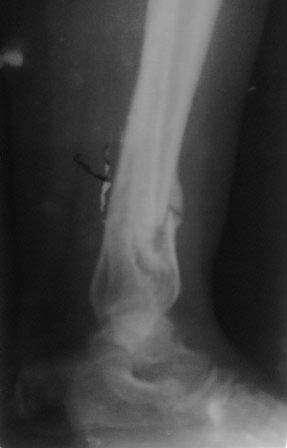

Пациентка 32 года, травму получила в результате ДТП, лечилась в гор.б-це №? Москвы с 19.07.по04.08.11г скелетным вытяжением, после наложена гипсовая повязка,(р-снимок 1,2.) после спадения отека гипс переведена в циркулярную, (видимо на другой вид лечения не хватило средств), гипс снят 19.11.11г(снимок-3) .Жалобы на боли при ходьбе через несколько шагов, увеличение отека в голени и г/стопном суставе, боли ноющего и неприятного характера, хромота, при осмотре отечность голени в с-н/з и г/с суставе, при пальпации умеренная болезненность в н/з голени, подошвенное сгибание в г/с суставе ограничена и болезненна. Работа связана с ходьбой, просить помочь чтобы не потерять работу. Пока в голове только КДО аппаратом Илизарова, уважаемые коллеги помогите советом! Доступно БИОС, пластины DCP. и прилагается последние р-снимки.